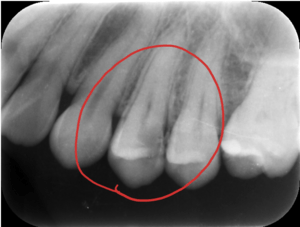

写真のレントゲンを見て頂くとわかると思います。赤丸の歯は、黒い影が歯の真ん中の黒い部分に達していますね。これが虫歯が歯の神経に達しているレントゲン写真になります。このような場合は、虫歯を取り除き歯の神経の治療が必要になり、その後に土台やかぶせ物の治療をします。

レントゲンは、柔らかければ柔らかいほど黒く写り、硬ければ硬い程白く写ります。そのため、虫歯は黒く写ってきます。

虫歯症例のレントゲン写真。虫歯は黒く写ります。